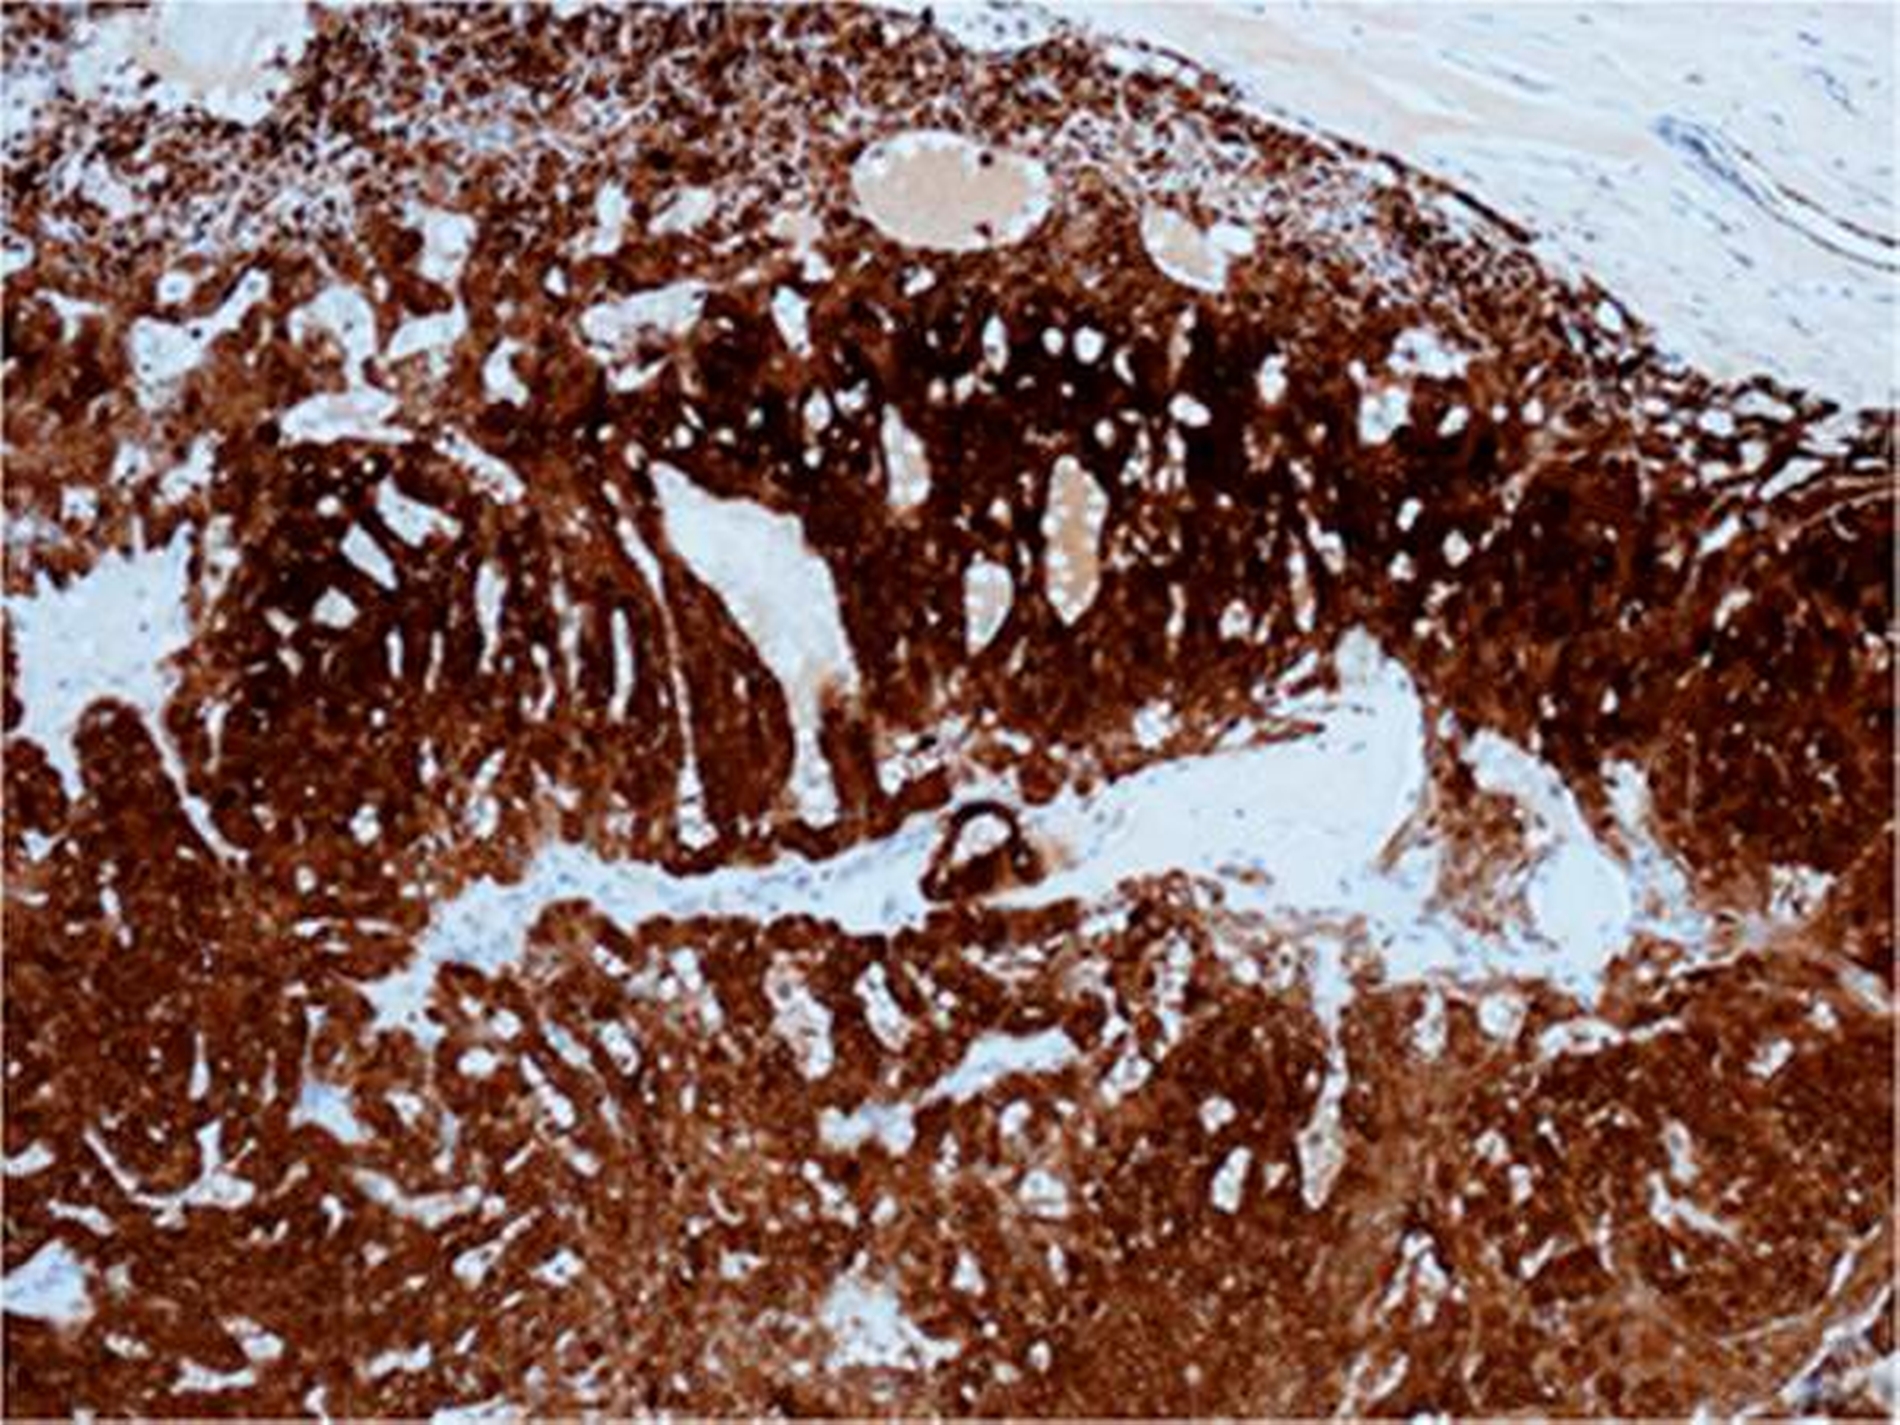

Der histologische Aufbau von Speicheldrüsen besteht generell aus unterschiedlichen Zelltypen (azinär, duktal, myoepithelial). Je nach Histogenese exprimieren deswegen Speicheldrüsentumore unterschiedliche immunhistochemische Marker. Beim polymorphen Adenokarzinom findet man epitheliale Antigene wie Zytokeratine, vor allem Zytokeratin 7 (100 Prozent der Fälle), p63 (100 Prozent der Fälle), Protein S-100 (97 Prozent der Fälle), BCL-2, gelegentlich CEA, alpha_SMA und Vimentin Cardesa, Mentzel, Rudolph, & Slootweg, 2009; Varun et al., 2015; El-Naggar et al., 2017].

Bei einer kleinen Biopsie kann eine Unterscheidung zwischen beiden auch unmöglich werden. Ferner können bei einem polymorphen Adenokarzinom sowohl benigne wie maligne Anteile nebeneinander vorkommen, wie auch dieses Fallbeispiel zeigt [Kämmerer, Kreft, Toyoshima, Al-Nawas, & Klein, 2009]. In seltenen Fällen kann es zu einer high-grade-Entartung kommen [Simpson, Pereira, Ribeiro, Abdulkadir, & Reis-Filho, 2002].

In der interdisziplinären Tumorkonferenz wurde postoperativ als adjuvante Maßnahme eine Bestrahlung empfohlen, diese wurde von der Patientin jedoch abgelehnt. Die histologische Aufarbeitung des Tumorpräparates ergab ein polymorphes Adenokarzinom.